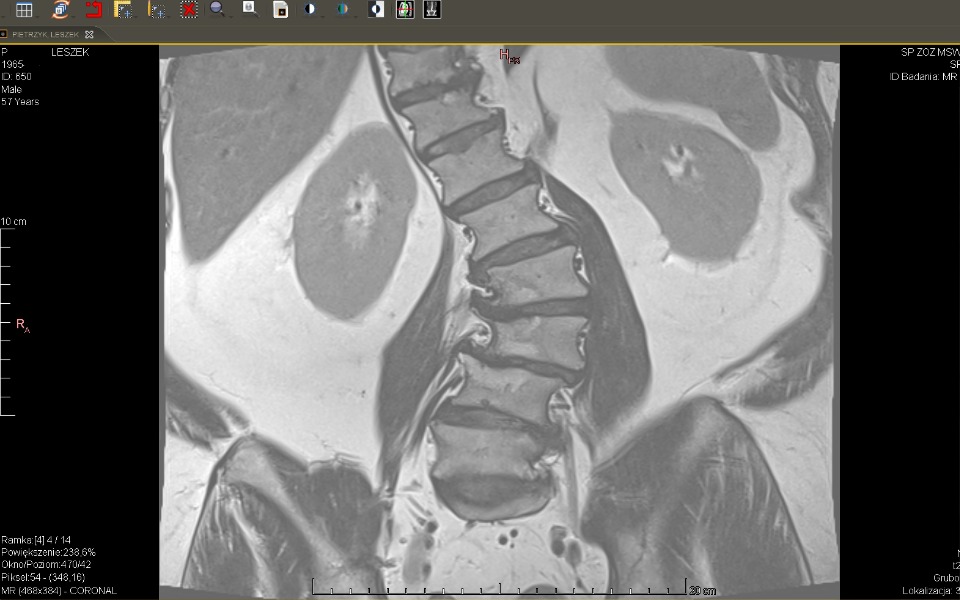

Nazywam się Leszek, jestem po operacji wymiany obu bioder, aż cud że kręgosłup wytrzymał pracę często po 12 godzin i dosyć ciężką fizycznie.

Operacja kręgosłupa jest bardzo ryzykowna, szanse 50 na 50% że się uda.